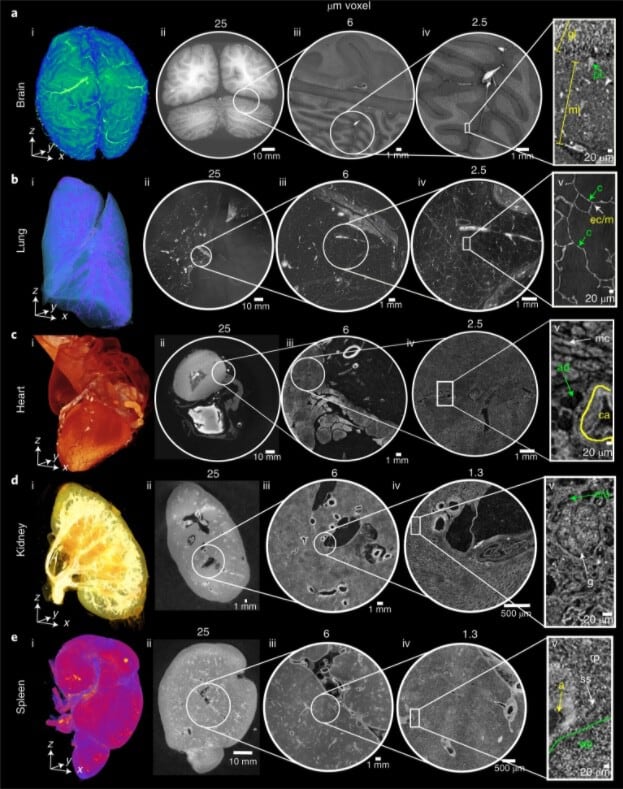

La nueva herramienta, descrita como una especie de “Google Earth del cuerpo humano”, permite a investigadores, médicos, estudiantes y público general recorrer los órganos desde su estructura global hasta las células individuales, sin necesidad de cortar o dañar los tejidos. La tecnología empleada fue bautizada como HiP-CT (tomografía jerárquica de contraste de fase, por sus siglas en inglés) y utiliza la fuente de radiación de sincrotrón más brillante del mundo, situada en el ESRF.

La técnica HiP-CT escanea órganos humanos intactos utilizando rayos X de sincrotrón, logrando imágenes de hasta una micra de resolución (HOA)

El avance central del atlas radica en la aplicación de la tecnología HiP-CT, que utiliza rayos X de contraste de fase generados por la fuente de sincrotrón ESRF-EBS, considerada 100.000 millones de veces más brillante que las fuentes hospitalarias convencionales.

Esta innovación permite escanear órganos humanos ex vivo de manera no destructiva y obtener imágenes con una resolución de entre 8 y 20 micras, llegando a hacer zoom en regiones específicas hasta el nivel de una micra, lo que equivale a 50 veces menos que el grosor de un cabello humano.

El método HiP-CT ya permitió identificar lesiones vasculares microscópicas en pulmones de pacientes fallecidos por covid-19, redefinir la comprensión de trastornos cardíacos y aportar información inédita sobre la patogénesis de enfermedades ginecológicas y renales. “En el riñón descubrimos que los glomérulos no están todos al final de la red vascular, como se creía, sino distribuidos de forma completamente distinta”, señaló Walsh.